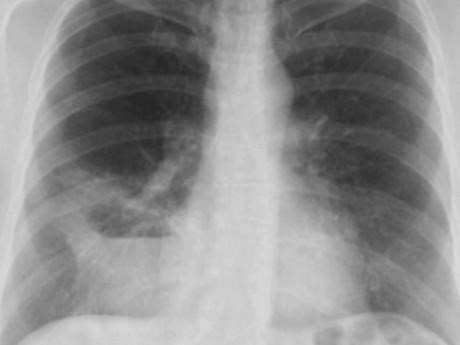

Phát bệnh từ 30 năm về trước, bà Trịnh Thị C (69 tuổi, Hà Nội) thường xuyên có những đợt ho khạc đờm kéo dài hàng tháng, một năm 3-4 đợt, điều trị có khi đỡ được 2-3 năm sau, tình trạng tái diễn.